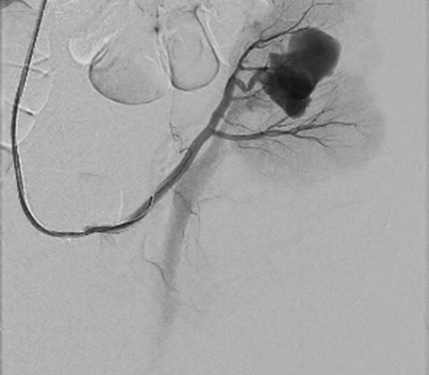

Right femoral artery was punctuated under local anesthetic. Inferior segmental artery was selectively cathe­terized and pseudoaneurysm was visualized. A microcatheter was inserted into segmental branch (Figure 4).

renal-36.png

Figure 4. Renal pseudoaneurysm catheterized and visualized using contrast solution